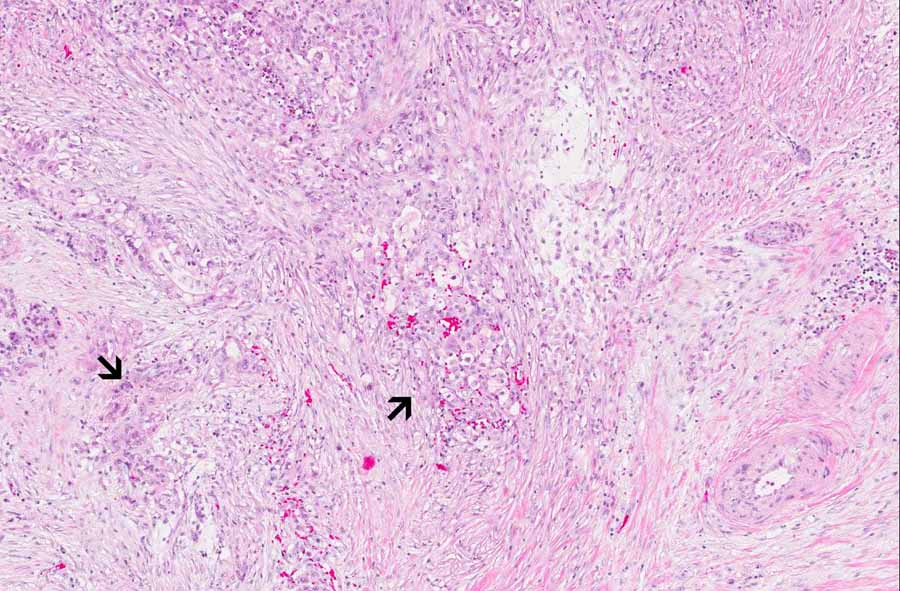

Area 2: The nerve (n) is surrounded and infiltrated by the tumor cells (t). Note that some of the neoplastic cells have lumen formation and this is a genuine feature of adenocarcinoma (arrow). Perineural invasion is a common finding in invasive ductal carcinoma of the pancreas. Note that the tumor cells are mucin producing.

Hematoxylin & eosin

• Perineural invasion (Area 2) is quite common in this case. You can see that the peripheral nerve is entirely surrounded by carcinoma cells.